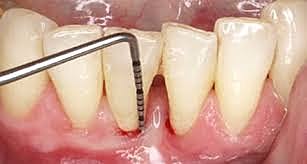

• SONDEO Y PRUEBAS DE SENSIBILIDAD

SONDEO Y PRUEBAS DE SENSIBILIDAD

Se usó sonda periodontal y periodontograma para registro de el sondeo y endo ice para prueba de sensibilidad, útiles instrumentos de diagnóstico.